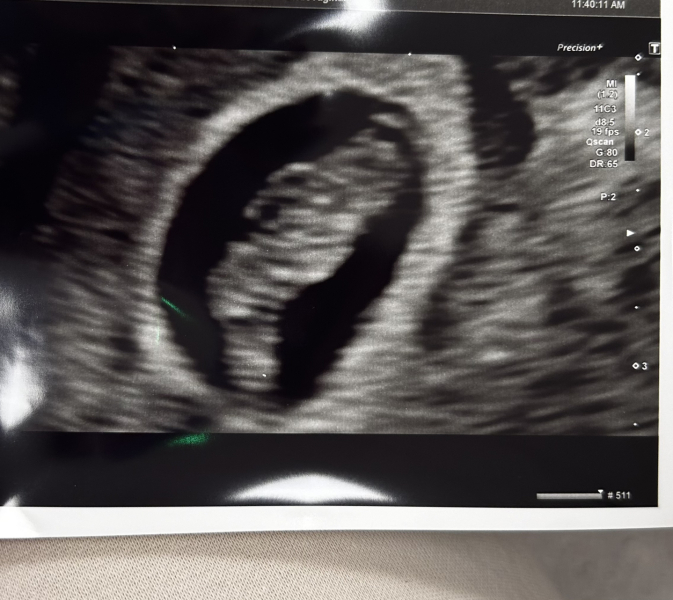

I have just been to the EPU and there's a healthy heartbeat and all looking 'perfect', no trace of bleeding in the uterus. They said I'm measuring 7+1 but my app says 8. I am trying not to overthink it too much as I do ovulate late but I'm still worrying. They reassured me and said they're not concerned at all. It brought us a bit of relief for now, but can't shake the anxiety.